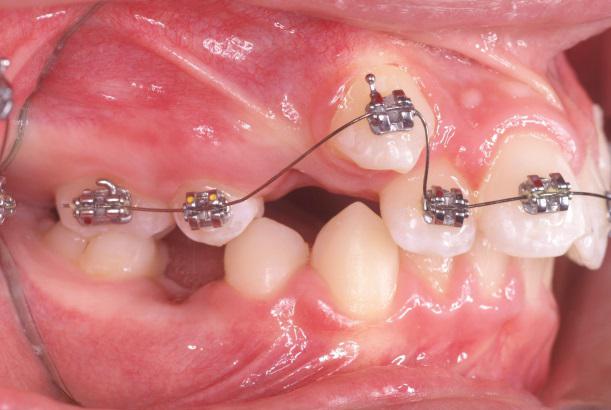

Bagues auto-ligaturantes

Les bagues sont maintenant auto-ligaturantes, il n’existe plus de ligature ( lien bloquant le fil orthodontique dans la rainure de la bague) l’avantage est pratique pour le praticien et moins de gène et une meilleure hygiène pour le patient.